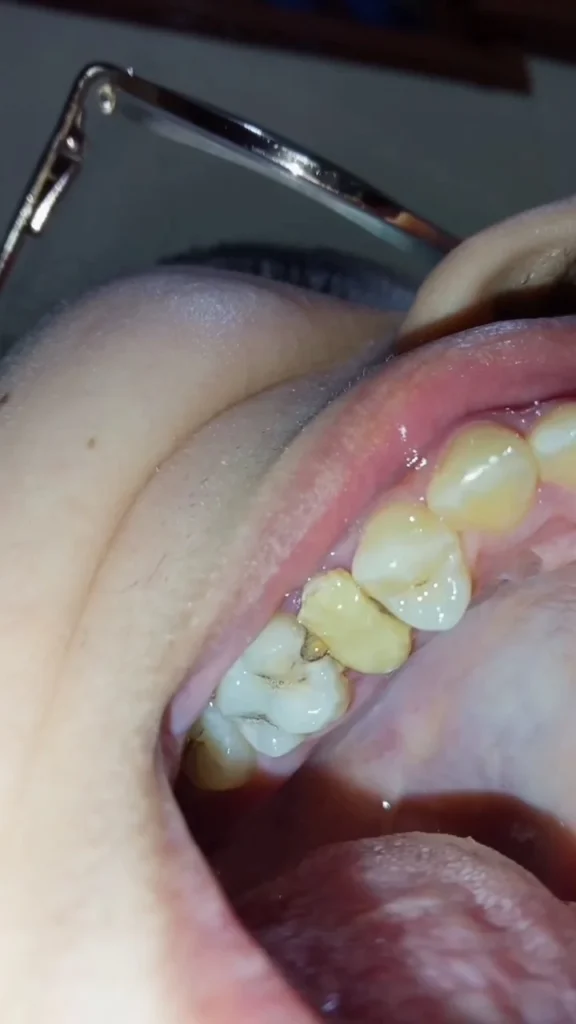

ضرس مثقوب و مسوس

Dentiste ? Connectez-vous et contribuez à la communauté dentaire au Maroc

Se connecterkan9tara7 3LIK twassel maaya f lkhass 0663700685 , consultation lowla fabour kanchof chno 3andek , n3tik le plan de traitement, lholol li kaynin et devis . o l9arar ki rja3 lik f lakher